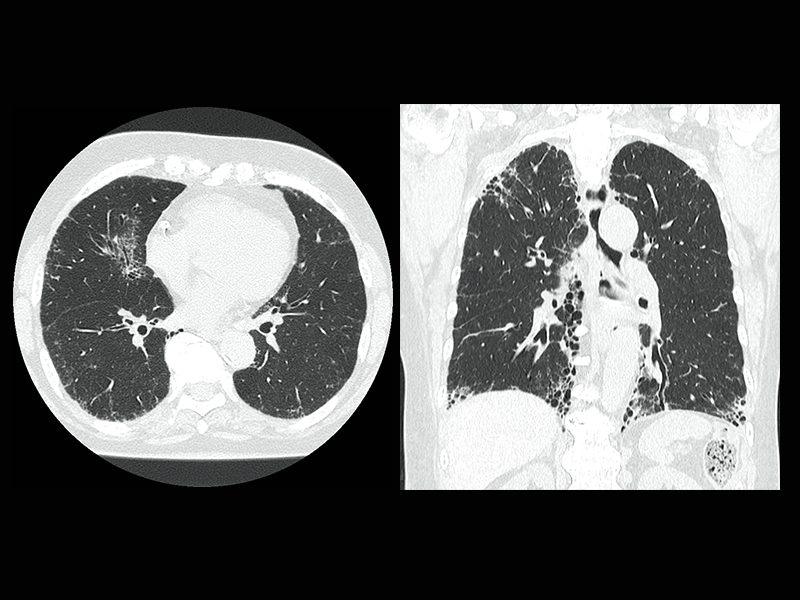

Interstitial pneumonia

Lung screening (CTDlvol: 2.0 mGy)

Non-tuberculous mycobacteria